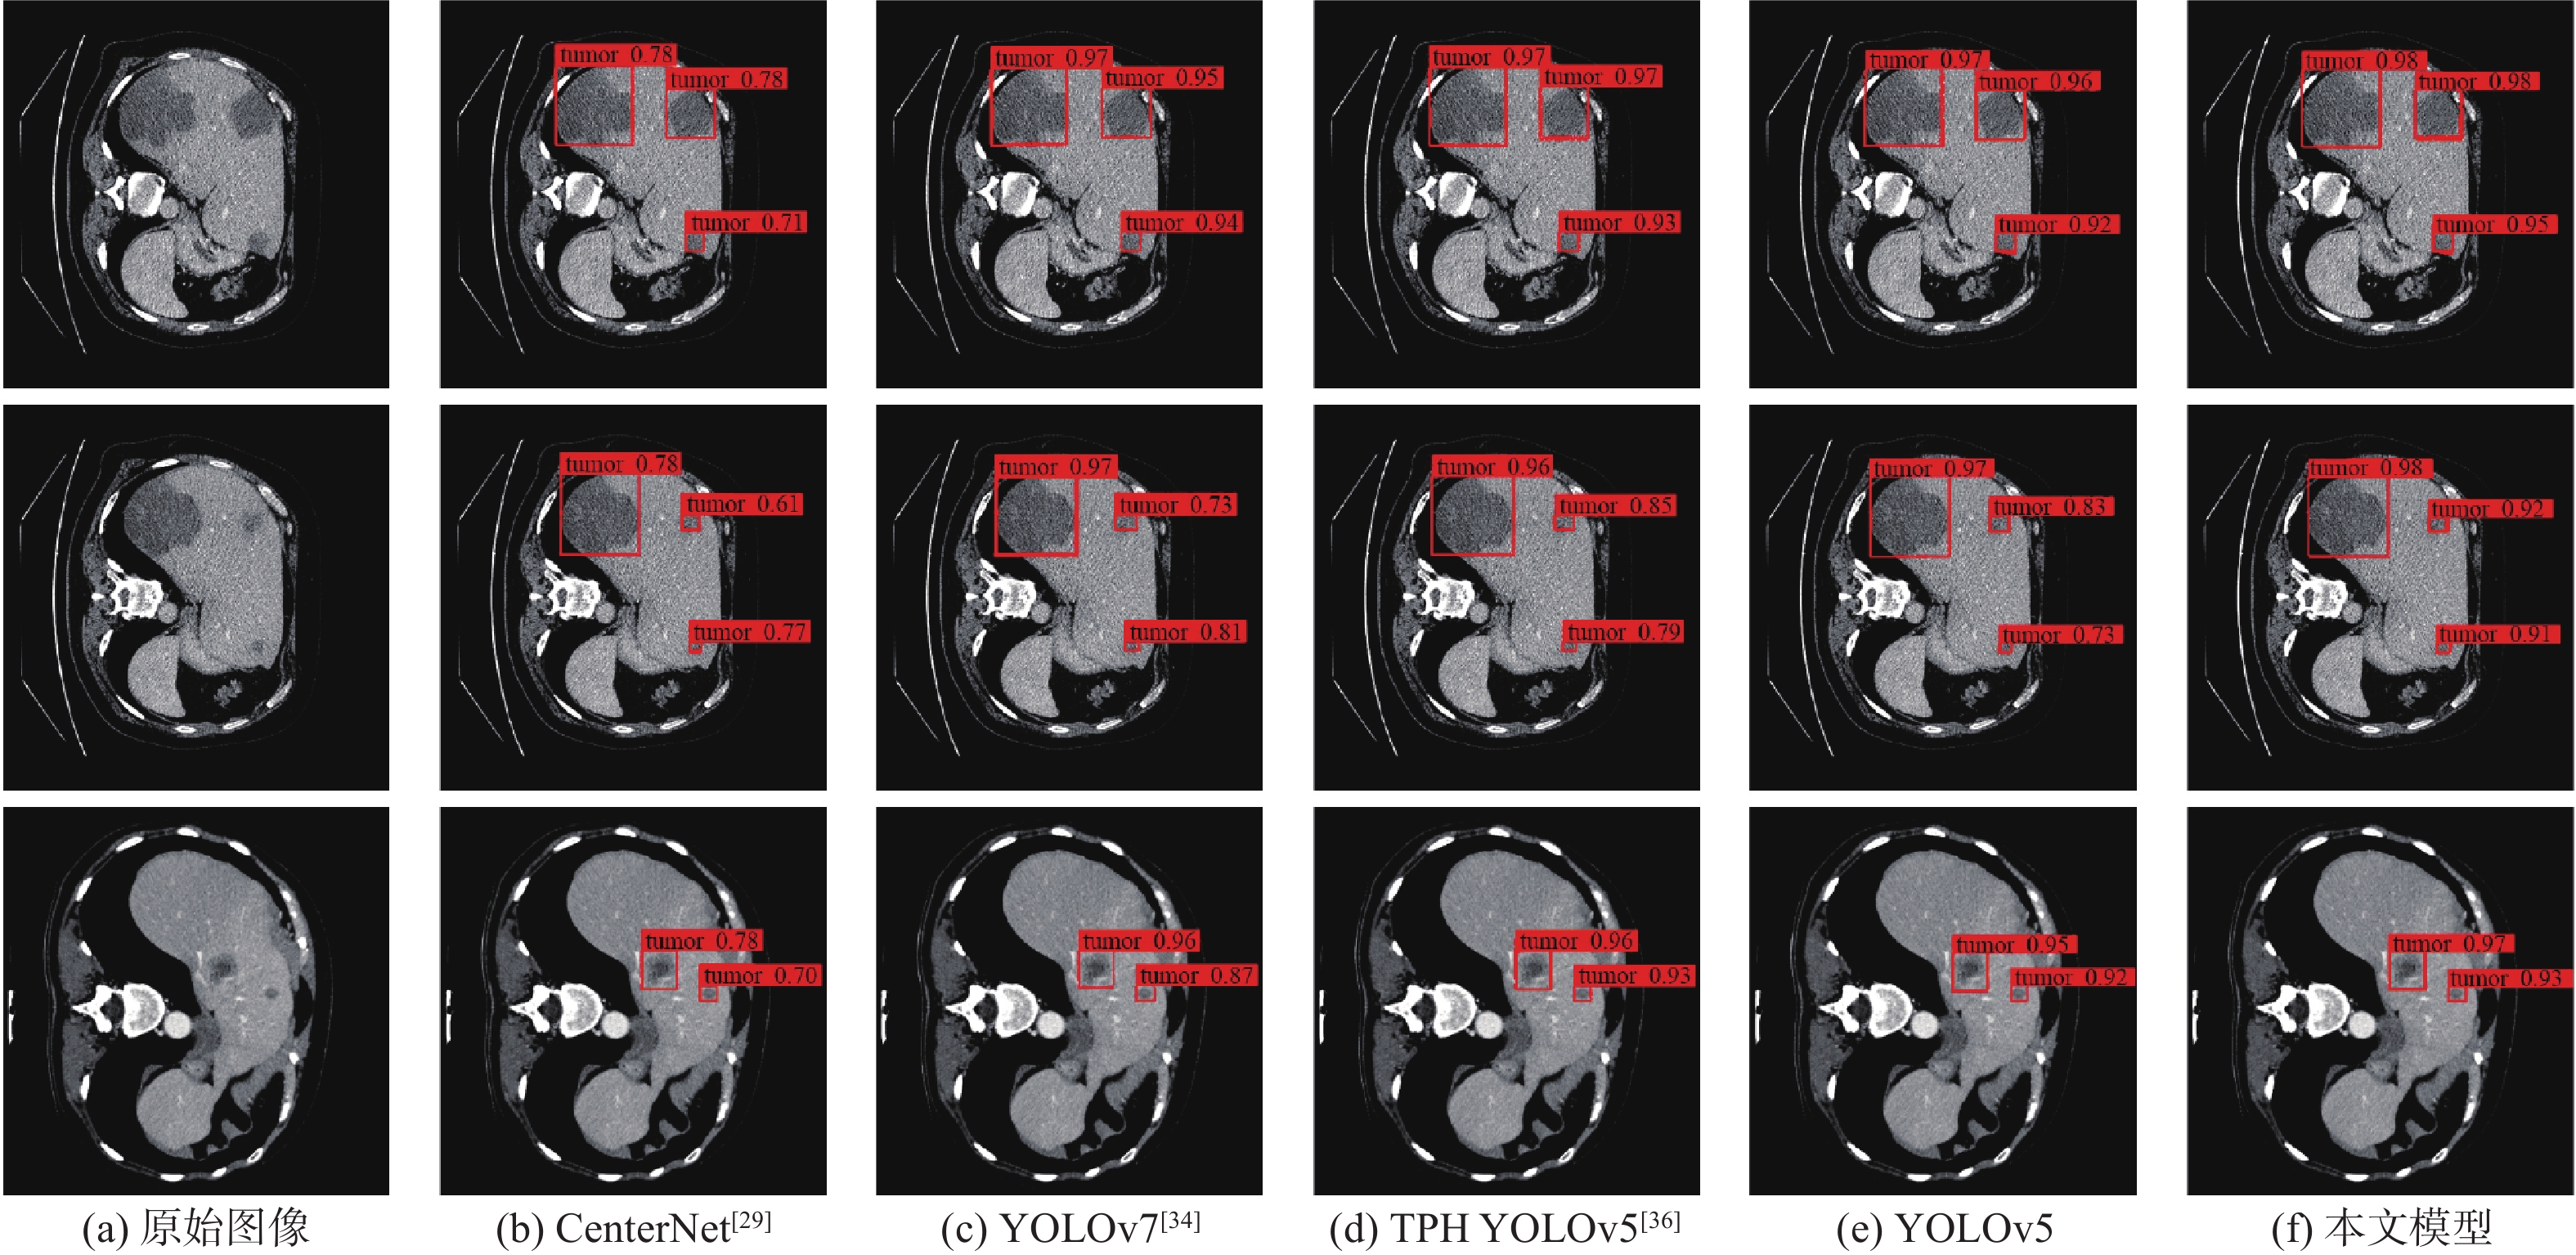

Damage detection method for aero-engine based on FDG-YOLO lightweight model

CAI Shuyu, HE Chong

2026, 52(4): 1055-1063. doi: 10.13700/j.bh.1001-5965.2024.0024

Abstract:

In response to the issues of poor real-time performance and low detection accuracy when deploying deep learning models for aero-engine damage detection on embedded devices, this paper introduces the FDG-YOLO lightweight model for aviation engine damage detection. Firstly, FasterNet was introduced to restructure the backbone network of YOLOv5, addressing the issue of large parameter count in the backbone network. Second, depth-wise separable convolutions were used to eliminate superfluous parameters in the neck network of YOLOv5 by improving ordinary convolutions. In order to improve the model's expressive power and receptive field, the original C3 structure was replaced with the GS C3 structure, which was built concurrently based on GSConv. Finally, experiments were conducted and validated on an aviation engine damage dataset. In the end, experiments were conducted and validated on an aero-engine damage dataset. The findings show that the FDG-YOLO model reduces the number of parameters by 52.5% and the giga floating-point operations per second by 66% when compared to the original model. On embedded devices, the mean average precision (mAP) reaches 89.6%, surpassing other lightweight models. The frames per second achieves 61, making the detection speed suitable for the engine damage image acquisition rate. It more effectively satisfies aero-engine damage detection's intelligent application criteria.